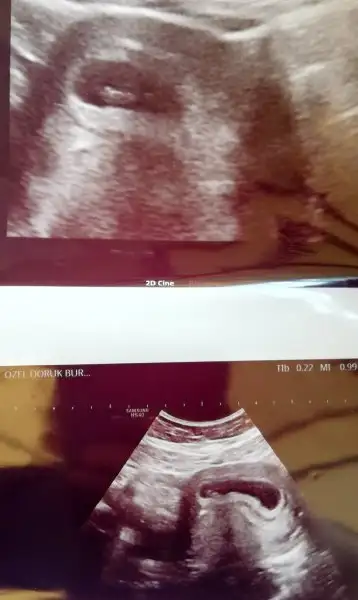

Benim sat 23 marttı bugün itibariyle 6 hafta+6 günlük yım :) kalp atışını kulağımızla duyamadık ekrandan gördük 12.haftada dinleyelim dedi herşey yolunda sağlıklı dedi doktor bakalım çok şükür allahım çok mutlu oldumay canım hadi inşallah güzel haberlerini bekliyorum .. yakındı galiba bizim satlar dimi?

maşallah canım gözün aydın olsun yok mu fotosuuu:)Benim sat 23 marttı bugün itibariyle 6 hafta+6 günlük yım :) kalp atışını kulağımızla duyamadık ekrandan gördük 12.haftada dinleyelim dedi herşey yolunda sağlıklı dedi doktor bakalım çok şükür allahım çok mutlu oldum

maşallah canım harika görünüyorr :)Sağlasın kuzummm benim bebiş aşağıda :)

Eki Görüntüle 2145012